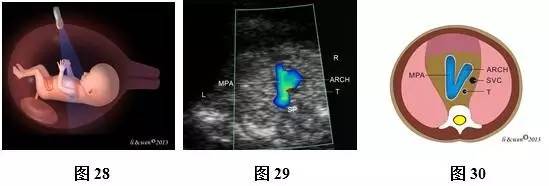

(二)11~13+6孕周胎儿心脏扫查方法及观察内容

超声扫查方法:声束从心尖部进入,在膈肌稍上方横切胸腔(图25),即获得心尖四腔心切面(图26,27);声束平面向胎儿头侧偏斜(图28),即可获得三血管气管切面(threevessels and trachea view,3VT,图29,30)图像。

标准切面判断标准:四腔心切面显示心脏四个腔室,可见二、三尖瓣启闭运动。3VT切面显示从左向右依次显示肺动脉、主动脉弓和上腔静脉,肺动脉和主动脉弓排列呈“V”形,两者血流方向相同。彩色多普勒血流成像对这些结构显示更清楚。

主要观察内容:四腔心切面主要观察心脏位置,心尖指向,心脏轴,左、右房室大小,房室瓣情况等。3VT切面主要观察肺动脉、主动脉弓、上静脉排列关系,血管数目,血管径线,血流方向等。

注:LV为左心室;RV为右心室;LA为左心房;RA为右心房;DAO为降主动脉;MPA为主肺动脉;ARCH为主动脉弓;T为气管;SVC为上腔静脉;R为右侧;L为左侧

图25~30 11~13+6孕周胎儿心脏扫查方法、观察内容及声像图及模式图。图25四腔心切面扫查模式图;图26、27四腔心切面彩色多普勒声像图及模式图;图28 3VT切面扫查模式图;图29、30 3VT彩色多普勒声像图及模式图